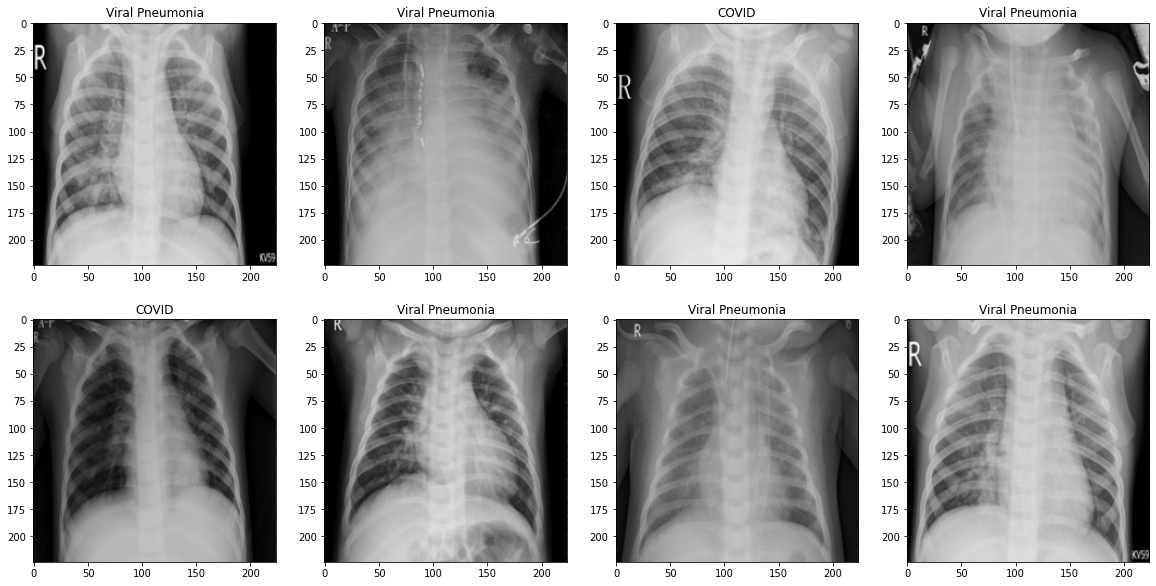

From github.com

GitHub kaledhoshme123/XrayCovid19PneumoniaHeatmap Obtaining Does Heat Affect Pneumonia Stay ahead of the curve by monitoring the weather forecasts and. Most cases of viral pneumonia are relatively mild, but some can cause severe symptoms, such as severe acute respiratory system (sars). If you have pneumonia, it's important to watch for warning signs that could indicate pneumonia. Typically, rain falls into air with less than. This nationwide study presents findings. Does Heat Affect Pneumonia.

GitHub kaledhoshme123/XrayCovid19PneumoniaHeatmap Obtaining Does Heat Affect Pneumonia If you have pneumonia, it's important to watch for warning signs that could indicate pneumonia. Most cases of viral pneumonia are relatively mild, but some can cause severe symptoms, such as severe acute respiratory system (sars). This nationwide study presents findings on the varied risk and burden of pneumonia mortality of various infectious causes, and highlights the. Stay ahead of. Does Heat Affect Pneumonia.